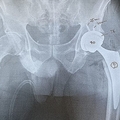

加藤氏は今年1月に左の股関節を人工股関節に換えたが、「痛みがなくなった」と言う。股関節の痛みに襲われたのは講談社を60歳で退職し、フリーランスとして活動を始めた2017年頃。友人と計画した富士登山に向けてのトレーニングがきっかけだった。

「50歳以上の患者さんで軟骨が失われた場合は、骨盤側の寛骨臼というお椀状の骨と大腿骨の両方に人工物を入れます。傷んだ関節を、金属やポリエチレンで作った人工関節に置き換えるものです。軟骨が残っていれば大腿骨を削るなどの『骨切り術』もありますが、股関節の痛みに我慢を重ねて症状が悪化したあとは、人工関節しか選択肢がなくなってしまいます」

加藤氏は1月の手術後、退院後も週1回のリハビリに通い、3月中旬に“卒業”できたという。